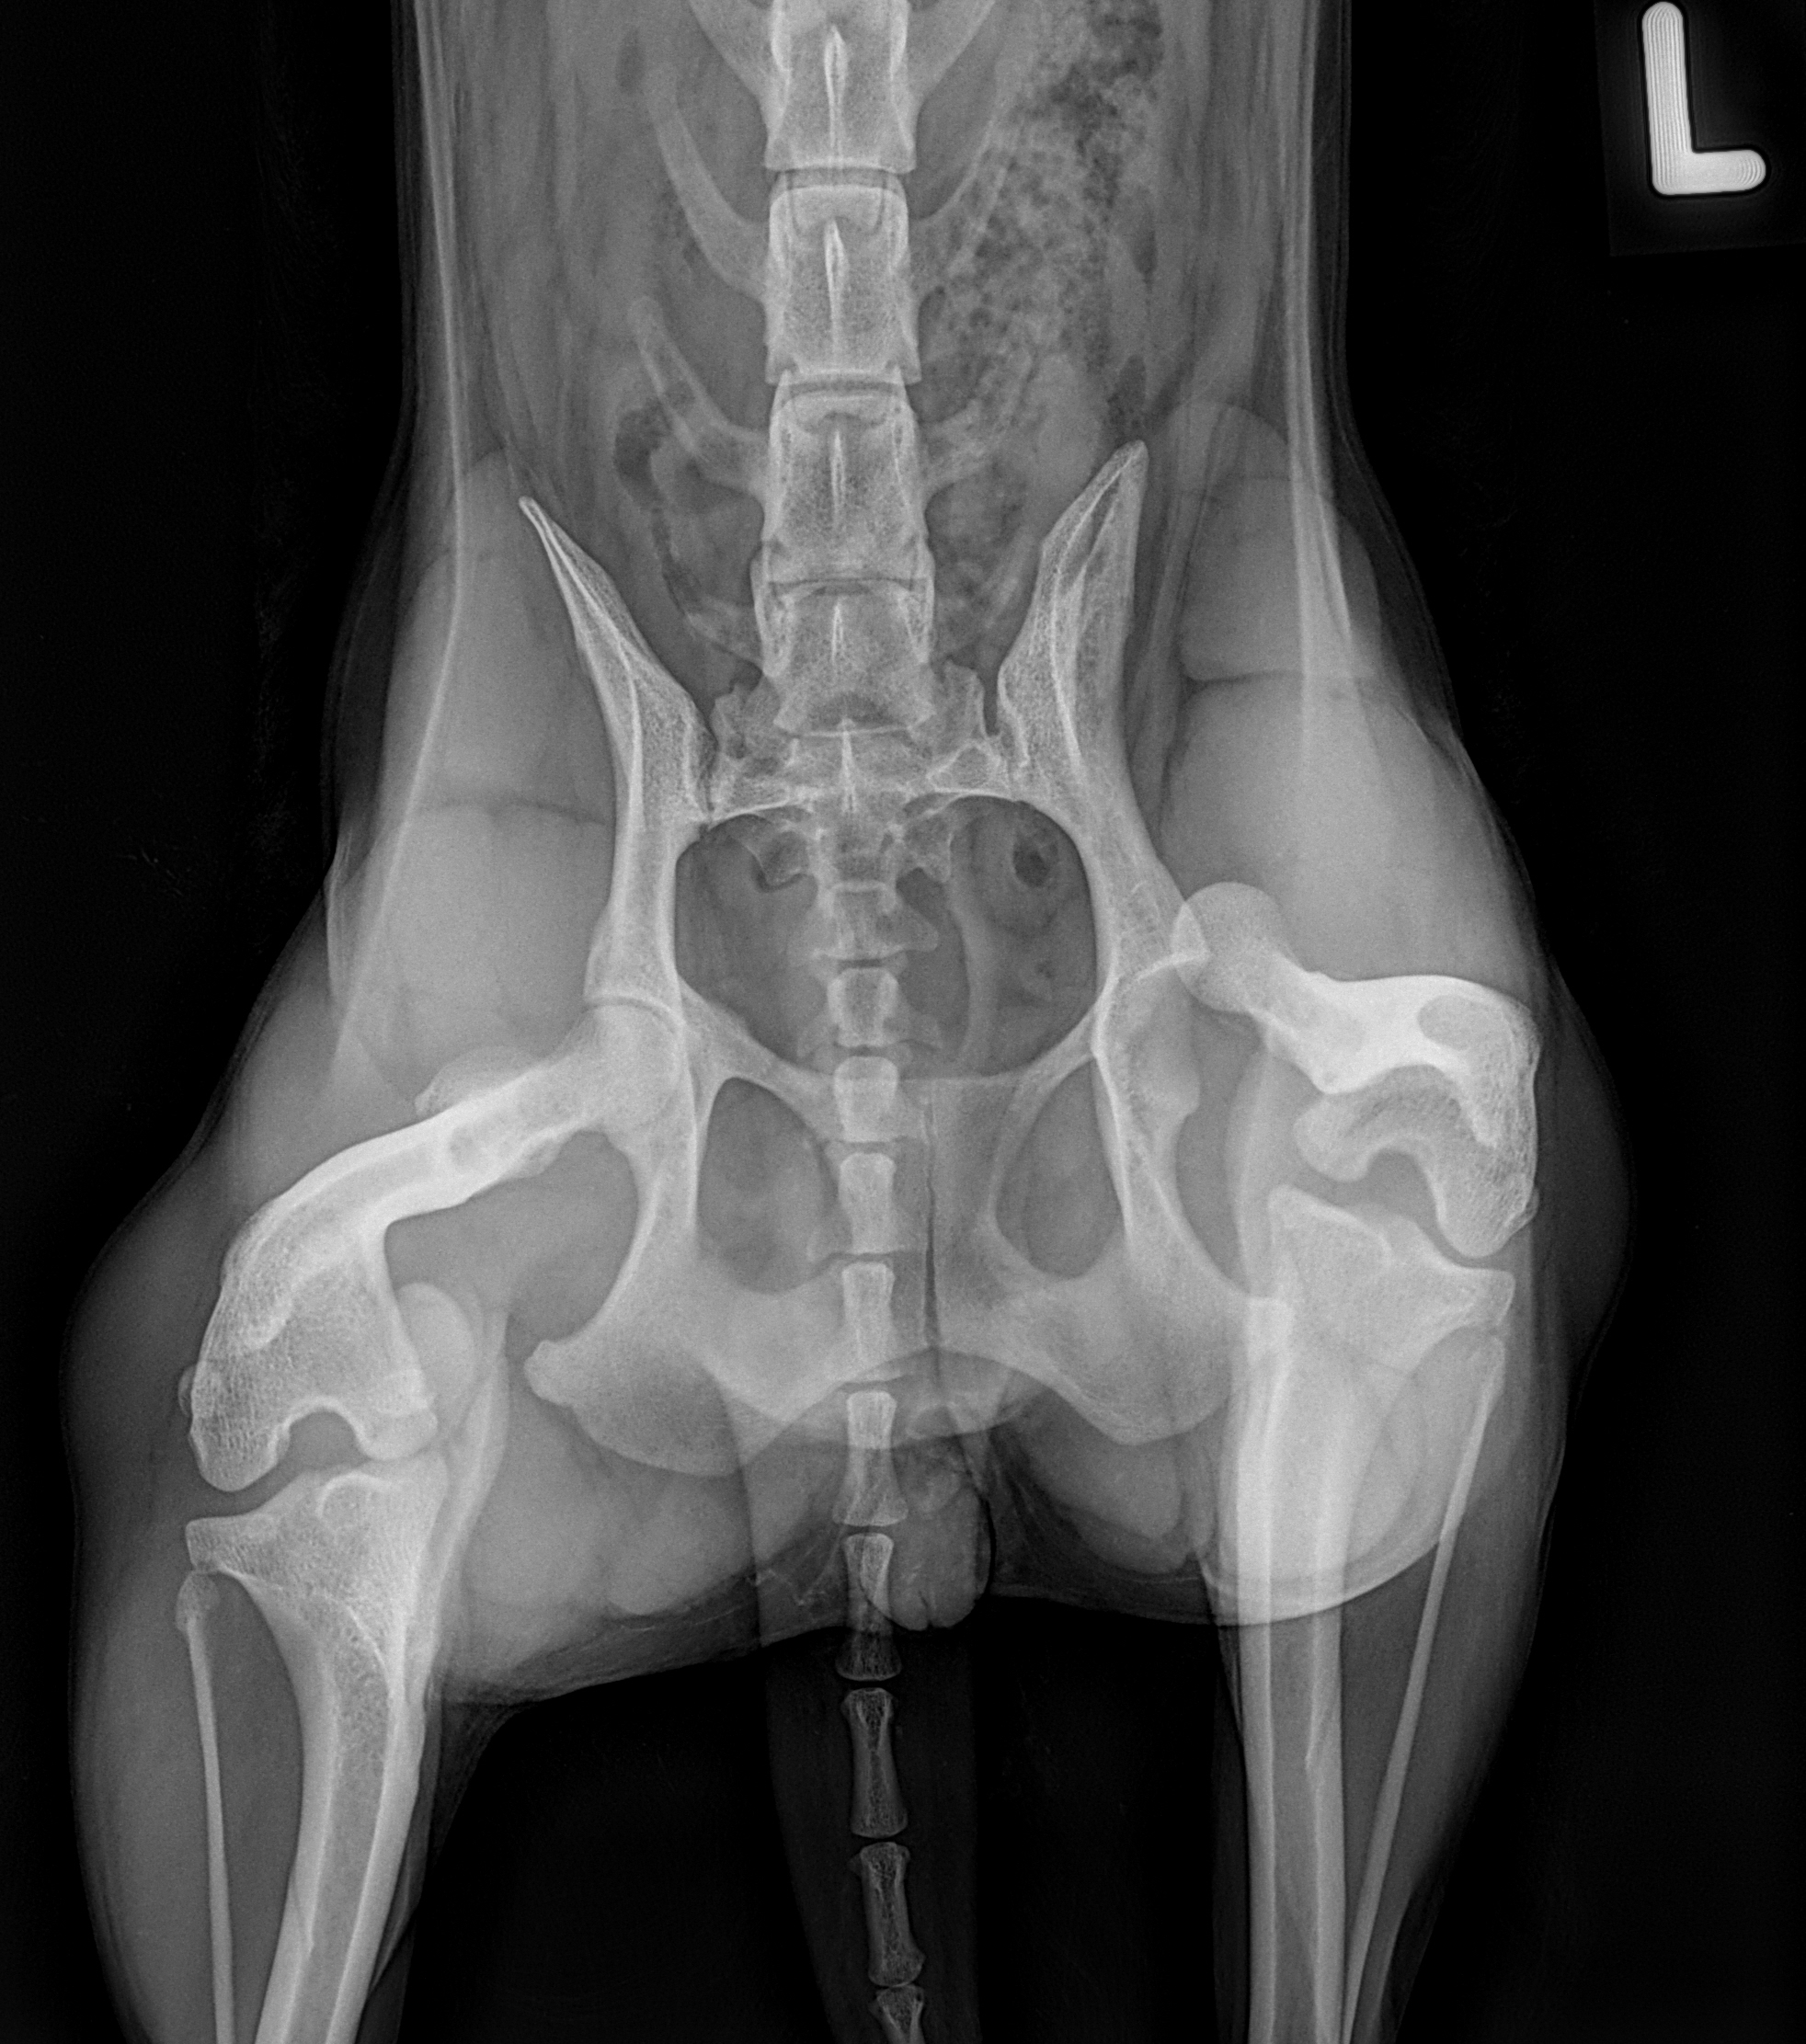

hat sich beim Spielen das Bein/Hüfte ausgekugelt. Heute war sie beim Chirurgen und liess es sich wieder einrenken. Hoffentlich hält es mit der Schlinge und sie kann sich eine OP sparen! Bitte helft, Daumen ganz fest drücken!